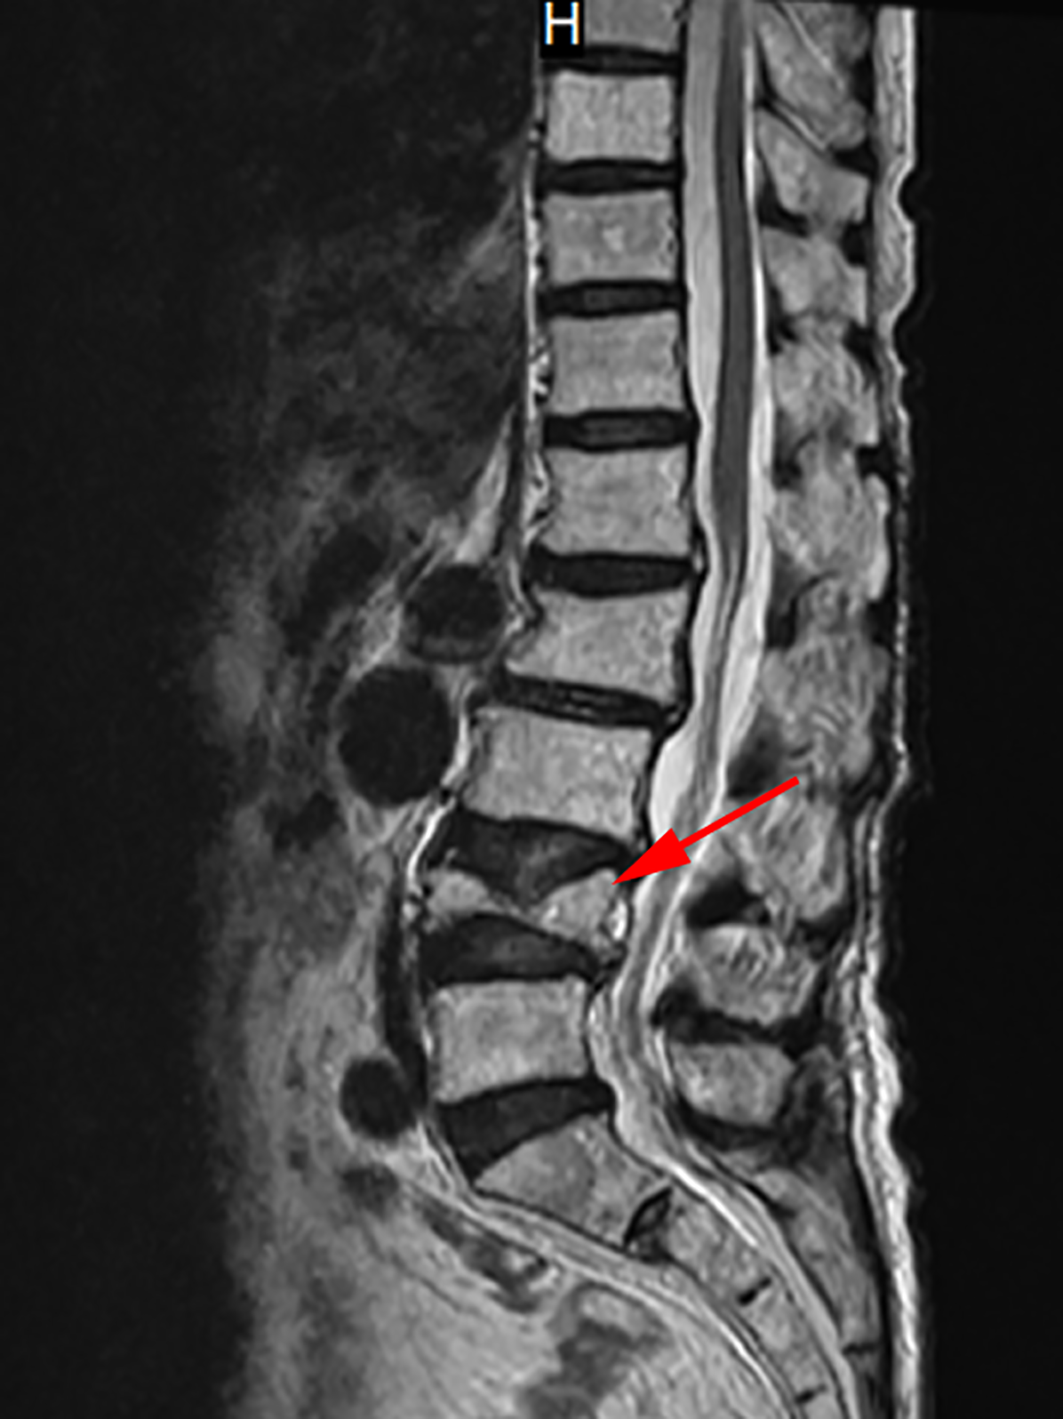

Therefore, the Department of Cardiovascular Medicine asked the Department of Endocrinology for a suggestion, considering recalcitrant hypocalcemia may have affected the management of heart failure. Reviewing her medical history, the patient presented to the spine surgery two weeks ago with lumbago and pain in both lower extremities that she had been experiencing for 1 year. Physical examination revealed a percussion tenderness on the protuberance of the 2nd and 3rd lumbar vertebrae, no radiating pain to the lower limbs, straight leg raising test (-), leg strengthening test (-), no abnormal muscle tension, and good peripheral blood supply of the limbs. In the absence of a history of trauma, magnetic resonance imaging (MRI) of the lumbar vertebra showed a compression fracture of the 4th lumbar vertebra and mild deformation of the 2nd lumbar vertebra (Figure 1). The spine surgeon checked the serum calcium and phosphorus, both within the normal range. Then the surgeon recommended bed rest and anti-osteoporotic therapy with denosumab 60mg ih, without calcium and vitamin D supplementation.

Figure 1

MRI of the lumbar vertebra. This image shows the MRI of the patient’s lumbar vertebra. The red arrow marks the 4th lumbar vertebra with a compression fracture.